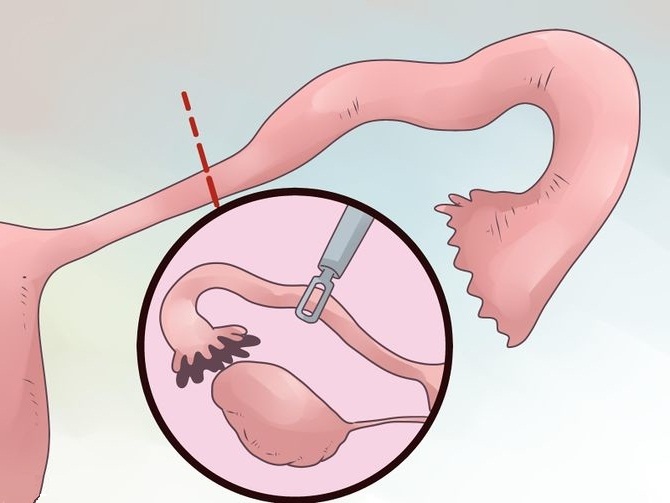

Современные методы лапаротомии и миомэктомии